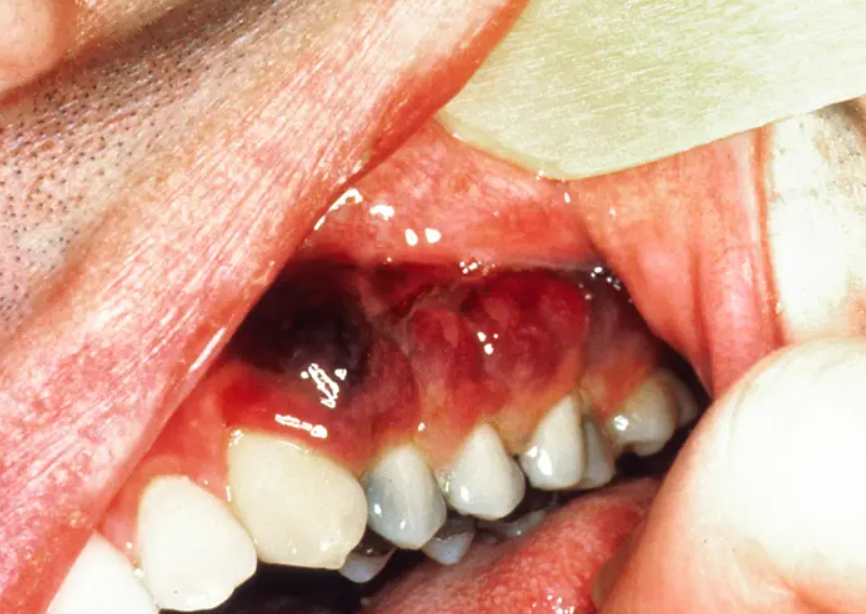

카포시 육종은 HIV AIDS 에 감염된 환자에서 주요한 사망의 원인이 되는 질환입니다.

림프관의 벽, 내피세포에서 기인한것으로 생각되는 방추형의 세포들로이루어진 종양 덩어리가,

서서히 자라는데, 이것이 피부나 점막에서 발견됩니다.

매우 드문 질환이나, 에이즈나, 장기이식 환자처럼 면역기능이 저하된 환자에서 발생하는 악성 종양입니다.

HHV human herpes virus 8 에 의해서 발생하는 악성종양으로, AIDS 환자에서 발견되는 경우는,

상당히 진행된 경우에 발생하며, 전신피부, 림프절, 위장관으로 병변이 퍼지면서, 사망률을 높이게됩니다.

초기에는 결막하 출혈과 유사하게 보이게되는데,

실제로는 아래쪽 결막 구석에 발생하는 선홍색의 혈관성 종괴로,

대개는 성장이 느려 작은 병변은 치료가 필요하지 않으나,

크기가 큰 병변은 방사선으로 치료하게됩니다.